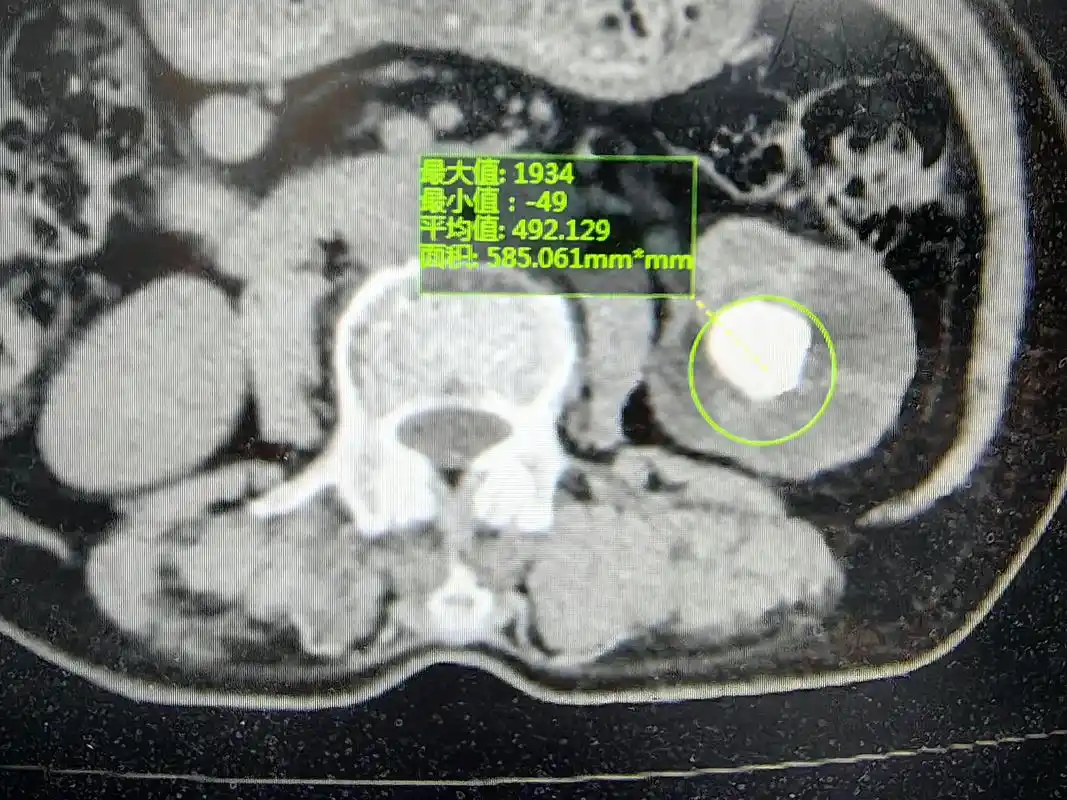

肾脏增强ct提示左肾错构瘤,红色标记处为错构瘤